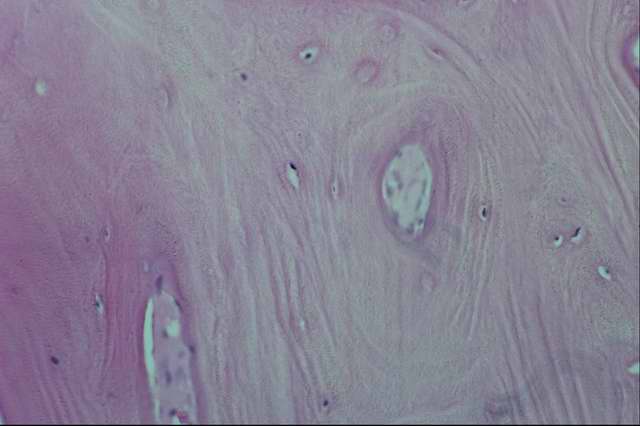

Гистологически гиалин обнаруживают в межклеточном веществе соединительной ткани. Системный гиалиноз стенок кровеносных сосудов и соединительной ткани проявляется образованием гиалина в основном веществе интимы и периваскулярной соединительной ткани артерий и капилляров. В конечном итоге образуется гомогенная плотная белковая масса, окрашивающаяся кислыми красителями. Хотя гиалин является индифферентным веществом, но накопление его сопровождается утолщением стенки сосуда, вытеснением медии гиалиновой массой с сужением просвета, вплоть до полного закрытия (облитерации) его в мелких сосудах. Некротизация тканей, подвергающихся гиалинозу, может сопровождаться кальцинацией их, разрывами стенки сосуда с возникновением кровоизлияний и тромбозов. В железистых органах гиалиноз соединительной ткани сопровождается утолщением базальных мембран желез, сдавливанием железистого эпителия с последующей его атрофией. Местный гиалиноз встречается в очагах хронического воспаления, во вновь образованной соединительной ткани (соединительнотканных капсулах и старых рубцах). При этом коллагеновые волокна набухают, сливаются в однородные ткани, а клетки атрофируются.